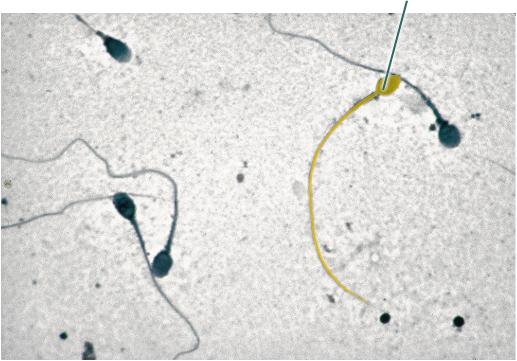

Identify the highlighted structure.

Sperm